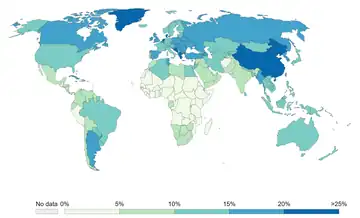

In 2000, smoking was practiced by 1.22 billion people, predicted to rise to 1.45 billion people in 2010 and 1.5 to 1.9 billion by 2025. If prevalence had decreased by 2% a year since 2000 this figure would have been 1.3 billion in 2010 and 2025.[290] Despite dropping by 0.4 percent from 2009 to 2010, the United States still reports an average of 17.9 percent usage.[61]

The WHO states that "Much of the disease burden and premature mortality attributable to tobacco use disproportionately affect the poor". Of the 1.22 billion smokers, 1 billion live in developing or transitional nations. Rates of smoking have leveled off or declined in the developed world.[294] In the developing world, however, smoking rates were rising by 3.4% per year as of 2002.[291]

The WHO in 2004 projected 58.8 million deaths to occur globally,[295]: 8 from which 5.4 million are smoking-attributed,[295]: 23 and 4.9 million as of 2007.[296] As of 2002, 70% of the deaths are in developing countries.[296]